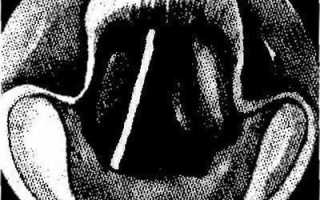

Туберкулезный инфильт рат на левой голосовой складке